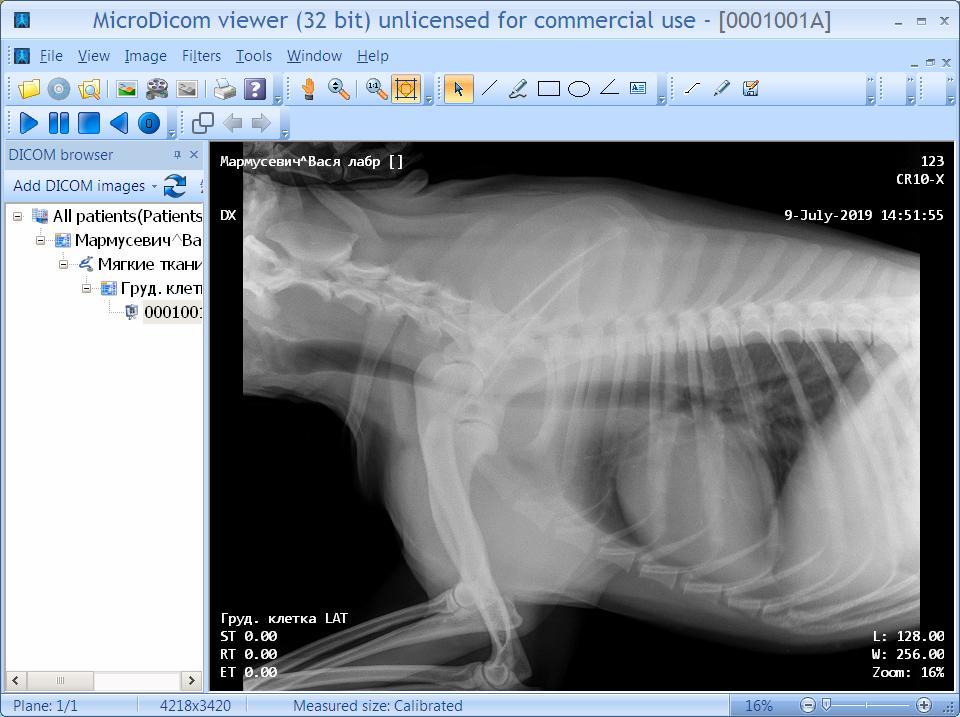

Настя Кузнецова Опубликовано 9 июля, 2019 Опубликовано 9 июля, 2019 (изменено) Очень надеюсь на помощь... Собака сначала чихала,потом появились приступы кашля. Сдали анализы,ничего не нашли. Сделали рентген в двух клиниках, но мнения врачей не совпали. Первый диагноз-коллапс трахеи,второй-обратное чихание. Очень переживаю. Надеюсь на вашу помощь. Спасибо! Изменено 9 июля, 2019 пользователем Настя Кузнецова

Азазелька и Локи Опубликовано 9 июля, 2019 Опубликовано 9 июля, 2019 Очень надеюсь на помощь... Собака сначала чихала,потом появились приступы кашля. Сдали анализы,ничего не нашли. Сделали рентген в двух клиниках, но мнения врачей не совпали. Первый диагноз-коллапс трахеи,второй-обратное чихание. Очень переживаю. Надеюсь на вашу помощь. Спасибо! Коллапс трахеи у крупных собак встречается очень редко, насколько я поняла, рентген-диагностика не особо информативна, Локи с этим просветила вдоль и поперёк. Сделали эндоскопию, не подтвердили. Приступы обратного чихания периодически бывают (видео можно погуглить), я ему носопырку закрываю (боковые щели) и отпускает.

Настя Кузнецова Опубликовано 11 июля, 2019 Автор Опубликовано 11 июля, 2019 Добрый день! Мы сегодня были у врача,пришли к выводу,что собаке нужно сделать трахеоскопию.,но немного позже,сейчас собака принимает препараты,которые значительно облегчили состояние,приступы исчезли. Сдали кровь,все в норме. Всем большое спасибо за советы,за неравнодушие! Обязательно напишу про наши дальнейшие шаги и результаты.

Настя Кузнецова Опубликовано 24 августа, 2019 Автор Опубликовано 24 августа, 2019 Здравствуйте! Обещала написать,как наши дела. Прошло 1.5 месяца. Состояние стабильное. После интенсивного медикаментозного лечения собака выглядит здоровой. Мы значительно сократили физическую нагрузку,на солнце не гуляем. Конечно,если бы сделать трахеоскопию...,но есть несколько существенных "но",поэтому сделаем только при жесткой необходимости. На данный момент диагноз - коллапс трахеи. Ну что ж,учимся с этим диагнозом уживаться. Желаю вашим питомцам здоровья! Спасибо)